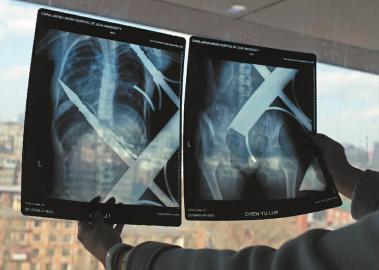

X光片顯示一根鋼筋將小女孩的右側(cè)肩膀刺穿,另外一根則從后背腰部以上靠近脊椎的地方穿入 白石 攝

在急診室的病床上,李紅旭看到了小雨。“她掛著吊瓶,意識(shí)比較清醒?!边M(jìn)一步觀察,李紅旭一時(shí)說不出話來———一根鋼筋穿透小雨右側(cè)肩膀,另一根則從后背腰部以上靠近脊椎的地方穿入,從小雨左肩部分穿了出來。兩根鋼筋由兩根角鐵連接,距離事發(fā),小雨背著這片鐵柵欄已經(jīng)近7個(gè)小時(shí)了。